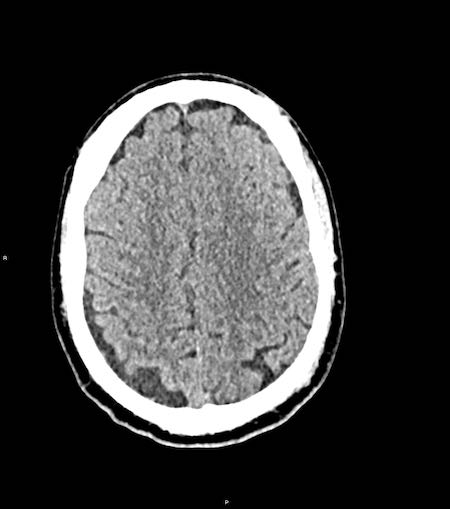

Tụ máu dưới màng cứng đồng tỷ trọng

Khi tụ máu dưới màng cứng tiến triển theo thời gian, tỷ trọng của khối tụ máu sẽ giảm dần và có thể tương đương với tỷ trọng của nhu mô não, khiến việc phát hiện tổn thương trở nên khó khăn.

Đây là trường hợp tụ máu dưới màng cứng đồng tỷ trọng rất khó phát hiện (các mũi tên).

Lưu ý rằng ở mức cắt cao hơn có tụ máu dưới màng cứng hai bên.